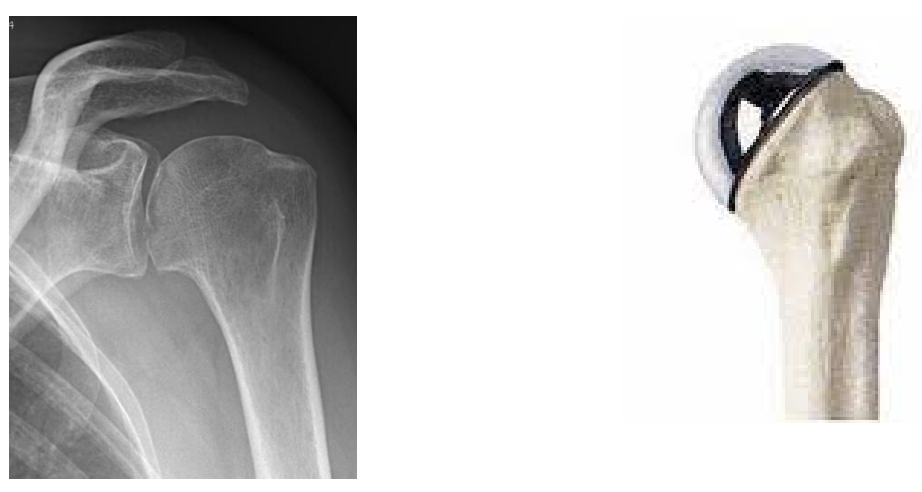

Totale schouderprothese (A1 – A2)

Is bedoeld om een ‘totale’ nieuwe bedekking te geven aan de bol én het kommetje van de schouder. Vaak nodig bij veralgemeende kraakbeenslijtage.

Resurfacing (B)

Als alleen het kraakbeen van de bol versleten is.

Fractuur prothese (C)

Prothese dewelke gebruikt wordt bij breuken van de schouderkop.